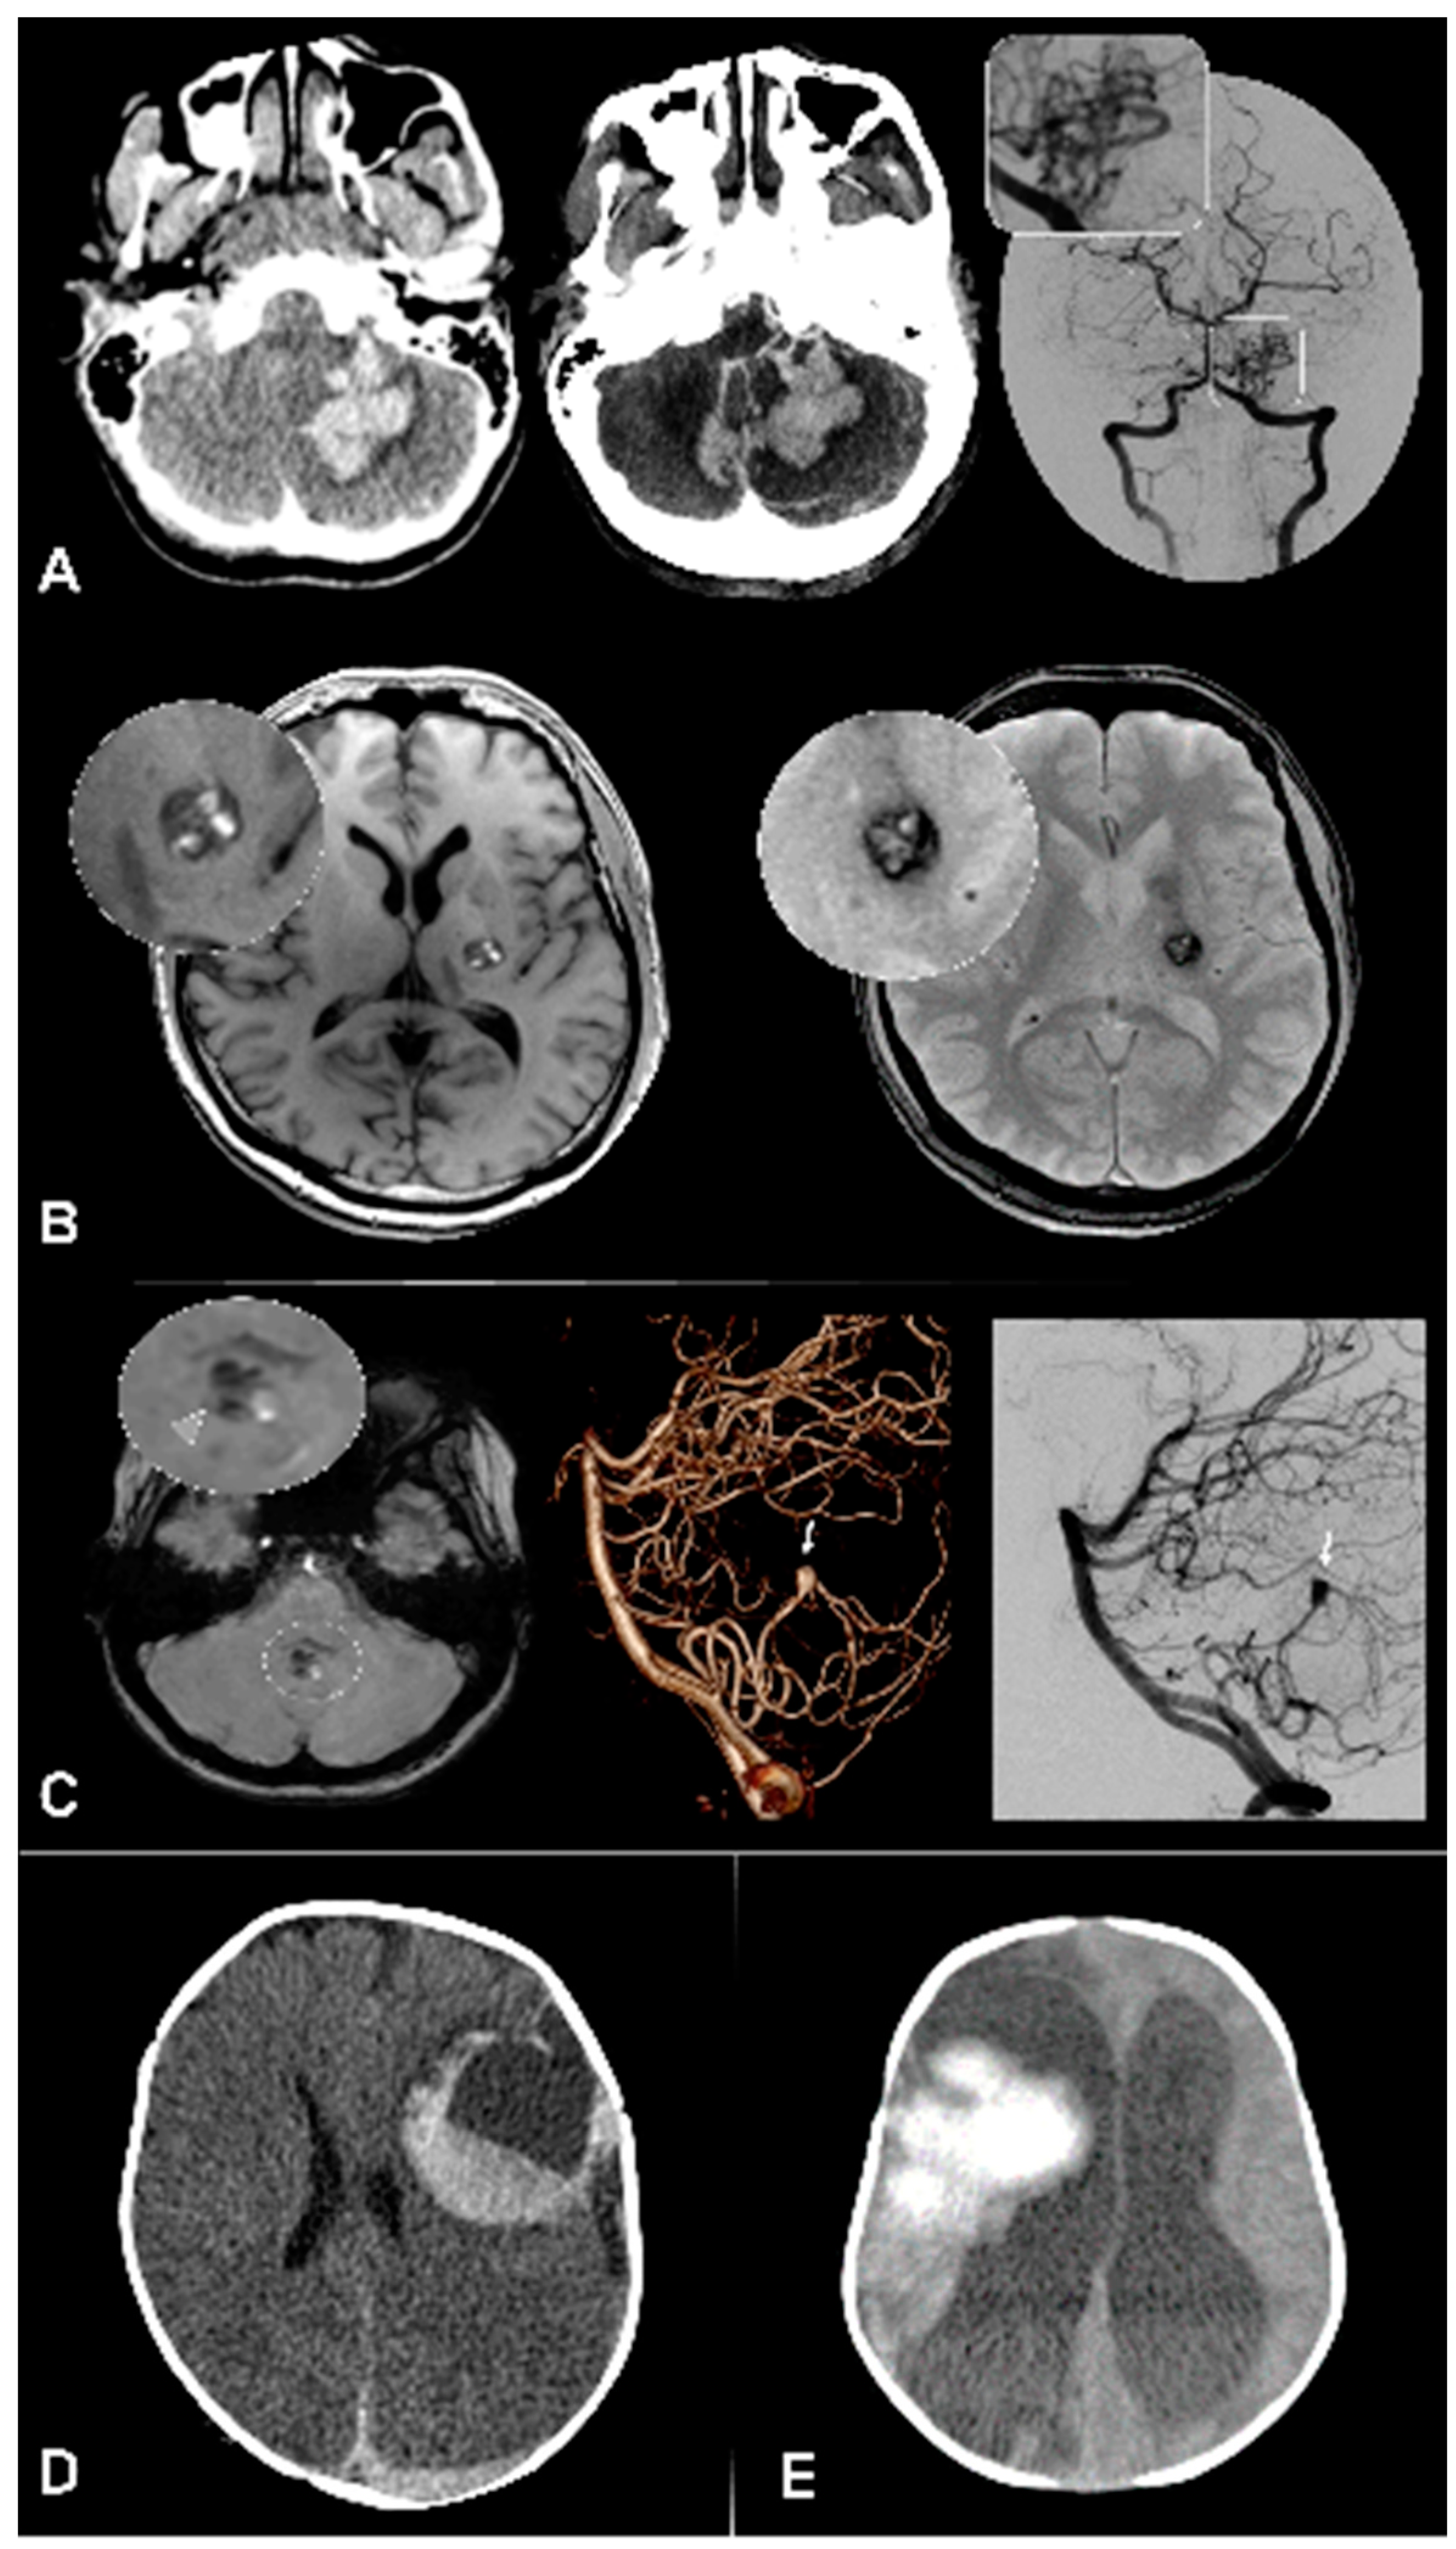

Digital subtraction angiography (DSA) has a central role for further characterization of vascular anomalies, and to investigate ICHs with undetermined etiology, due to its higher spatial and temporal resolutions and consequent higher sensitivity for intracranial shunts detection. (Figure 1 and Figure 2) The optimal timing for DSA realization is unknown, but should theoretically be performed as soon as possible in children with ICH of unknown origin to identify and treat occult vascular malformations. Of note, DSA is a low risk and often high yield examination in children: a recent analysis of pediatric patients revealed a 0% complication rate during the procedure and a 0.4% postprocedural complication rate [21,22].

CTA/MRA are often used as first screening for aneurysms [37,38]; however, DSA is still the gold standard with highest detection rates (97% of patients versus 80% of the time without DSA), especially for the detection of small aneurysms under 4 mm [11,39,40,41]. An important advantage of DSA is the possibility to perform rotational angiographies and thereby create 3D reconstructions of every aspect of the aneurysm. This allows for a highly detailed depiction of the aneurysm anatomy, enabling for best possible planning of therapeutic strategies [42]. Moreover, for example in anterior communicating aneurysms the contralateral ICA and A1 can be depicted and merged with the ipsilateral side to plan endovascular therapy [43].

Figure 2. Vascular imaging in pediatric ICH. Admission non-contrast CT with intracerebral hemorrhage (asterisk). Corresponding CTA shows evidence of large aneurysm of the right MCA. In the MRI (bottom row and right panel)) of the same patient, TOF-angiography does not clearly show the aneurysm. The DSA clearly visualizes aneurysm morphology.